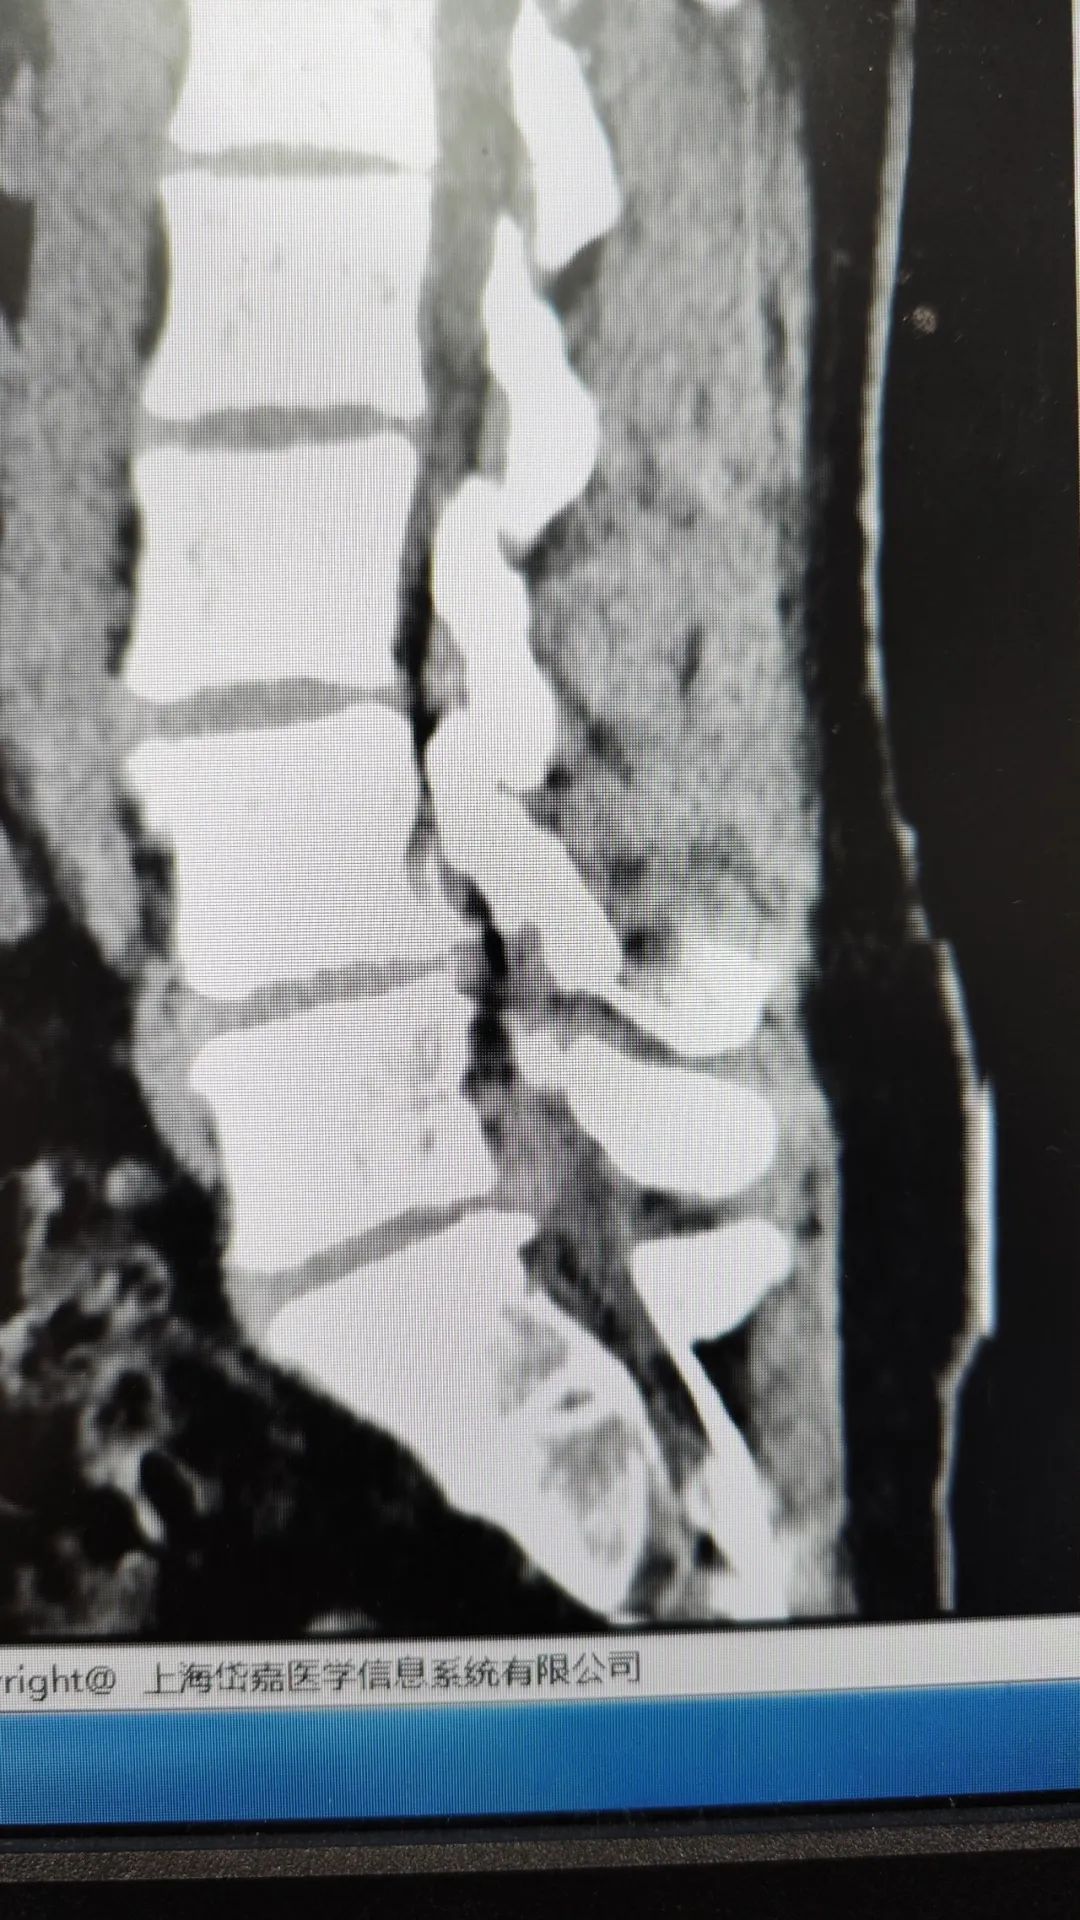

虽然缺乏核磁,但顾昕副主任在仔细阅读X线片和CT后,也有了对小张病情精确诊断的把握。只有游离的髓核才会引起这么剧烈的疼痛,患者腰椎4-5节和腰5骶1节都有突出,但是腰5骶1节有游离髓核表现,是引起患者疼痛的腰突节段,非常适合做脊柱微创内镜手术。对于脊柱内镜已有10年3000例的经验的顾昕副主任来说手术本身并没有太大难度。